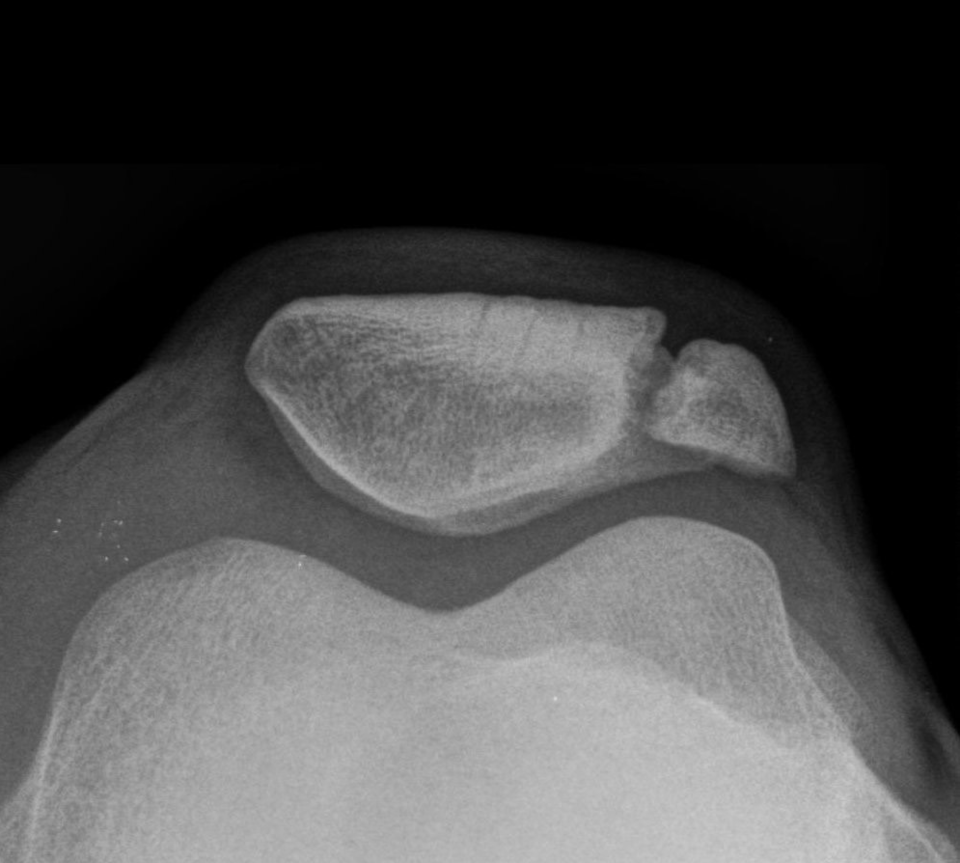

Das Patellaspitzensyndrom (M. Sinding-Larsen-Johansson) ist quasi der weibliche M. Osgood-Schlatter mit einer Osteonekrose der Patellaspitze. Das Patellaspitzensyndrom (M. Sinding-Larsen-Johansson) ist quasi der weibliche M. Osgood-Schlatter mit einer Osteonekrose der Patellaspitze. © wikimedia/nomen 49